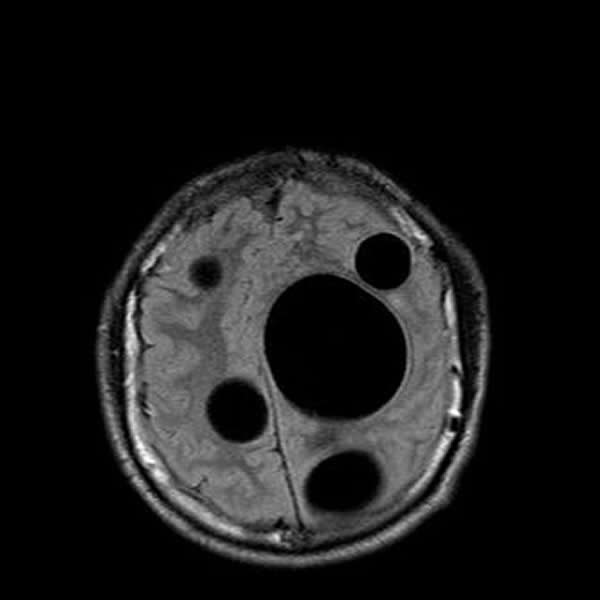

16 años, debilidad en miembro inferior derecho y caida de cabello